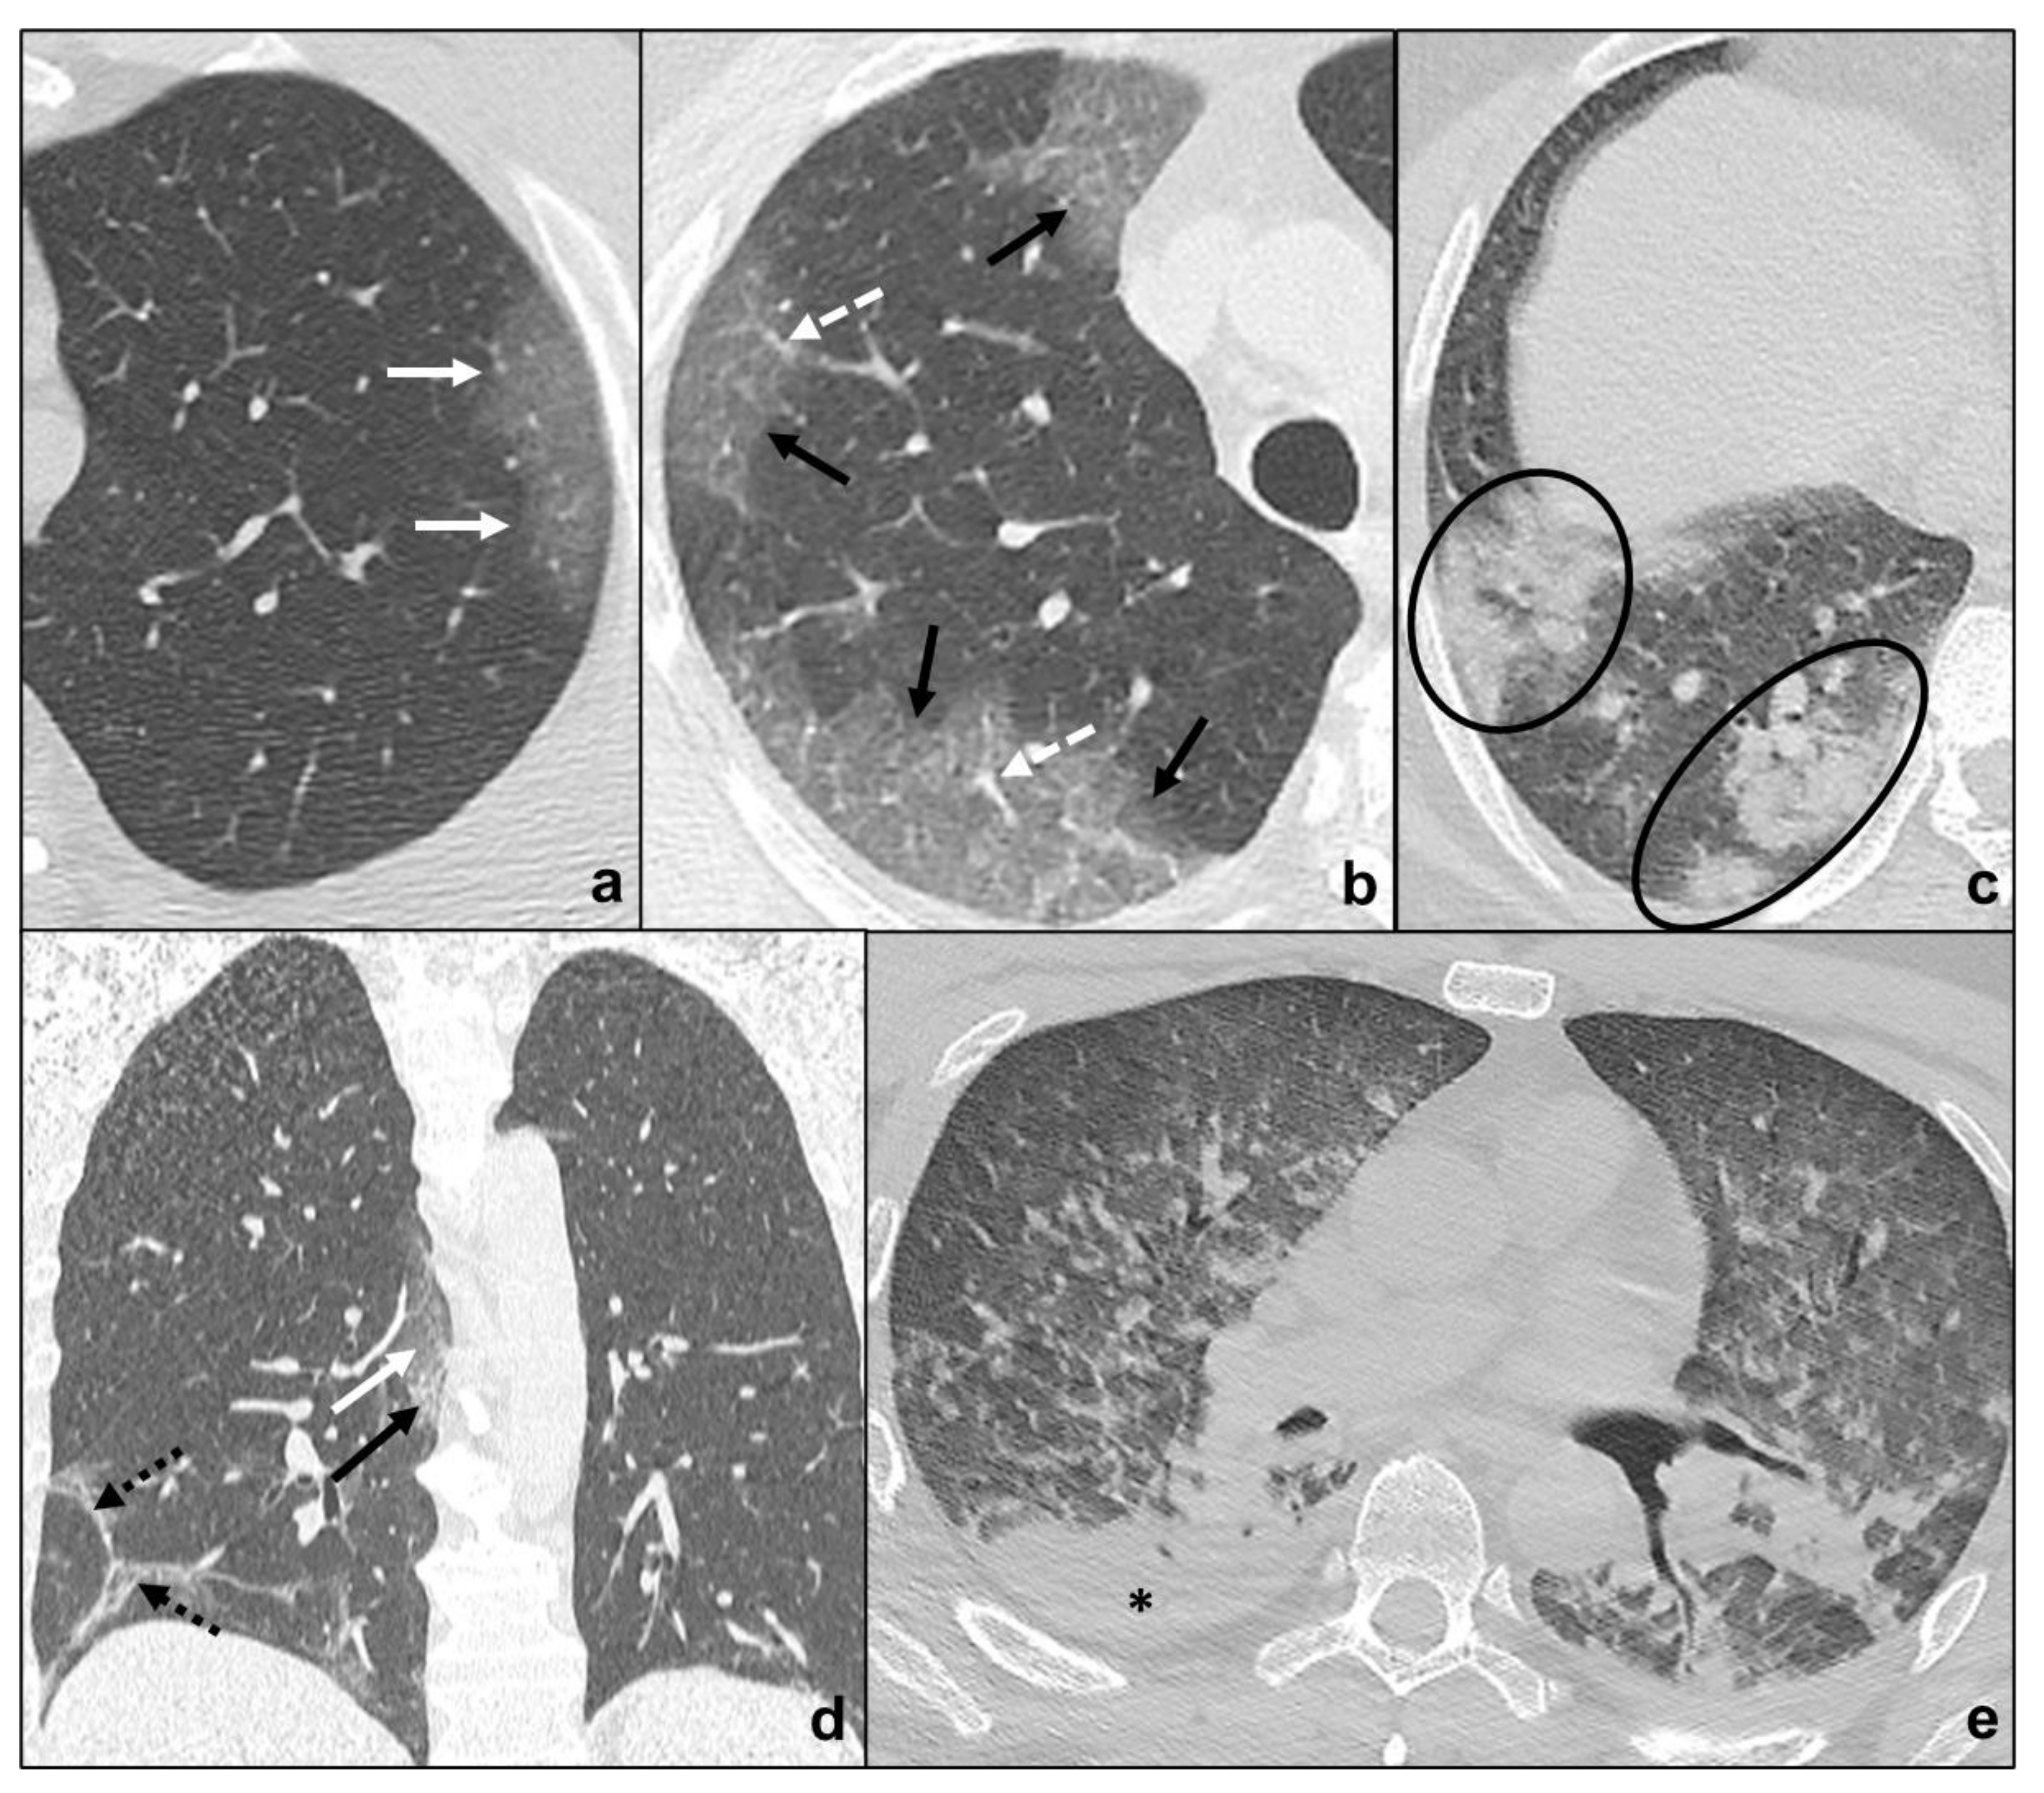

COVID-19 pneumonia has been divided into four stages, and the transition between two stages may carry overlapping findings [13] (Figure 1, Table 1):

Figure 1.

COVID-19 Pneumonia phases and possible evolutions. In (a), a subpleural ground-glass opacity (white arrow in (a)) indicating phase 1 is appreciable; in (b), extensive subpleural crazy paving pattern (black arrow in (b)) is preferrable to phase 2 and white dotted arrows indicate peripheral pulmonary vessel widening; in (c), consolidations (black circles in (c)) suggest phase 3; in (d), irregular consolidations coexisting (black dotted arrows in (d)) with ground glass opacities (black arrow in (d)) and crazy paving (black arrows in (d)) represent phase 4; in e, ARDS, a possible complication of COVID-19 pneumonia, presenting with asymmetric dependent consolidations (black asterisk in (e)) and widespread confluent ground glass opacities.

- Early phase/Stage 1 refers to days 0–4, and ground glass opacities represent the main radiological findings (Figure 1a);

- Progressive phase/Stage 2 refers to days 5–8, and the hallmark is represented by crazy paving pattern (Figure 1b) coexisting with extensive ground glass opacities and initial consolidative foci;

- Peak phase/Stage 3 is typical of days 9 to 13, and CT shows consolidations (Figure 1c), sometimes surrounded by a ground glass halo (halo sign);

- Absorption phase/Stage 4 starts around day 14, and ground-glass areas together with linear consolidations are appreciable (Figure 1d).

Opacities are typically bilateral and subpleural with an apicobasal gradient of distribution. Additional radiological features are peripheral pulmonary vessel widening, while pleural effusions, pulmonary nodules, and mediastinal lymphadenopathy are rare findings [13,14,15].

Clinical conditions may worsen suddenly, and patients may show wheezing, hunger for air, tachypnea with reduced blood oxygen saturation. These features indicate COVID-19 pneumonia progression to ARDS (acute respiratory distress syndrome) [13,16]. ARDS radiologically presents on HRCT with patchy confluent areas of ground glass and dependent consolidations with a typical antero-posterior gradient [17]. Clinical and radiological monitoring are keys to the early identification and treatment of ARDS in COVID-19 pneumonia. HRCT is extremely sensitive to identify disease progression and complications, but it exposes patients to high radiation doses, is not cost-effective, and decontamination is far longer and more complex. On the other hand, chest X-ray is less sensitive, but cost and time effective with the advantage of easier decontamination [10,12]. For these reasons, chest X-rays may be used to monitor disease progression. The sudden onset of typical ARDS symptoms together with the identification of the abovementioned radiological features which do not match patients’ COVID-19 pneumonia phase should always be regarded as a possible sign of complications, such as ARDS.